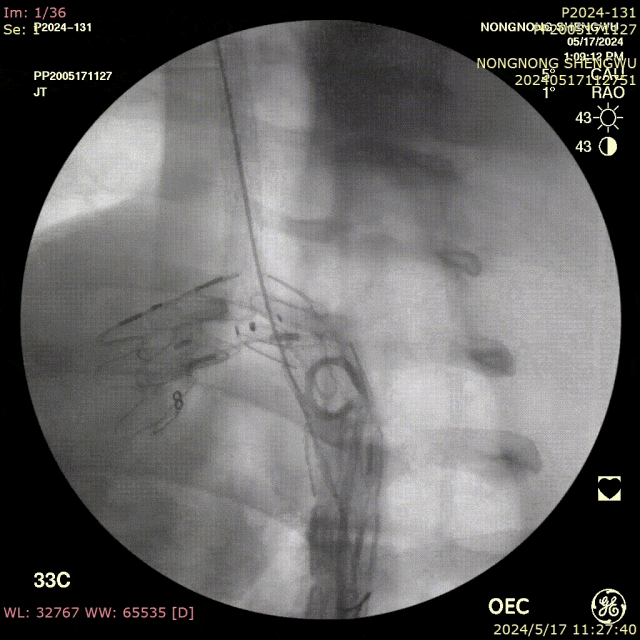

我们在两头35kg巴马公猪中完成动物实验:

成功实现弓上分支的快速、准确原位开窗;

破膜过程流畅,无分支或主动脉损伤;

取出标本可见圆形破口、支架贴合良好,证实技术可行性。

动物实验

巴马公猪35kg

标本